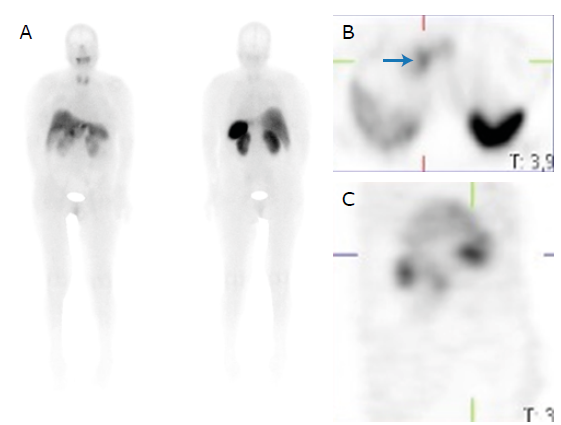

On the third day of admission, and given the high suspicion of a VIPoma, a somatostatin receptor scintigraphy was performed (Figure 2), which showed a lesion proximal to the pancreatic head with somatostatin receptor expression; therefore, management with subcutaneous octreotide 100ug every 8 hours was immediately started, resulting in complete resolution of the diarrhea within 24 hours. Due to the patient's improvement, 4 days after admission to the ICU, she was transferred to the general floor.

Somatostatin receptor scintigraphy showing uptake at the level of the pancreatic head (blue arrow) and no evidence of metastatic hyperenhancement. A) Anterior and posterior plane; B) Axial plane; C) Sagittal plane.

Figure 2: Somatostatin receptor scintigraphy showing uptake at the level of the pancreatic head (blue arrow) and no evidence of metastatic hyperenhancement. A) Anterior and posterior plane; B) Axial plane; C) Sagittal plane.

Source: Document obtained during the course of the study.